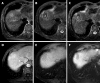

A wide range of local thermal ablative therapies have been developed in the treatment of non resectable hepatocellular carcinoma (HCC) in the last decade. Laser ablation (LA) and radiofrequency ablation (RFA) are the two most widely used of these. This article provides an up to date overview of the role of laser ablation in the local treatment of HCC. General principles, technique, image guidance and patient selection are discussed. A review of published data on treatment efficacy, long term outcome and complication rates of laser ablation is included and comparison with RFA made. The role of laser ablation in combination with transcatheter arterial chemoembolisation is also discussed.